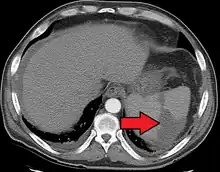

| Splenic infarct seen on CT | |

An abdominal CT scan is the most commonly used modality to confirm the diagnosis,[3] although abdominal ultrasound can also contribute.[5][6][7]